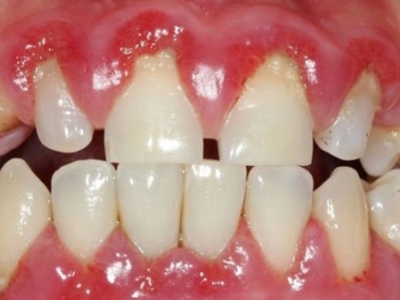

牙龈炎是发生于牙龈组织的炎症,患者可出现牙龈出血伴肿胀、发红、正常形态改变和偶尔不适等症状。本病主要由口腔卫生状况差导致,包括口腔不洁、牙菌斑等,诊断依据临床检查,治疗包括专业牙齿清洁和加强家庭口腔卫生。

牙龈炎可先引起牙齿与牙龈之间的沟(龈沟)加深,然后牙龈充血,炎症围绕一个或多个牙齿,伴牙龈乳头肿胀和易出血。一般无痛,可自行消退,也可维持轻度炎症数年。

牙龈炎常见的病因是口腔卫生差,不良的口腔卫生使牙菌斑沉积于牙齿与牙龈之间,造成龈沟加深,另外牙结石、不良修复体等也可造成牙龈炎的发生。